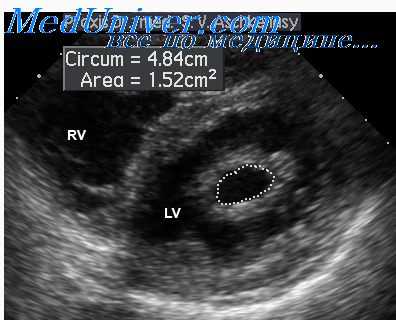

Визуализация пищевода при использовании стандартных ультразвуковых методик затруднена. Однако использование двойного допплеровского контроля улучшает диагностику заболеваний пищевода. На первом этапе исследования проводится сканирование в области эпигастрия через область пищеводного отверстия диафрагмы в горизонтальном положении и, в отдельных случаях, с запрокинутой головой. На втором этапе проводится заполнение желудка водой в количестве 300 - 500 мл для оптимизации осмотра пищевода и стенок желудка, выявления ГЭР, а также измерение диаметра пищевода в момент глотка.

Визуализация пищевода обычно возможна на протяжении 1,5-2,5 см брюшного отдела. За нормальный диаметр пищевода у детей приняты значения 7-10 мм. Диаметр нижней трети пищевода более 11 мм (во время глотка 13 мм) может указывать на формирование СГПОД. При диаметре более 13 мм (во время глотка 15 мм и более) заключение о СГПОД у детей становится практически достоверным.